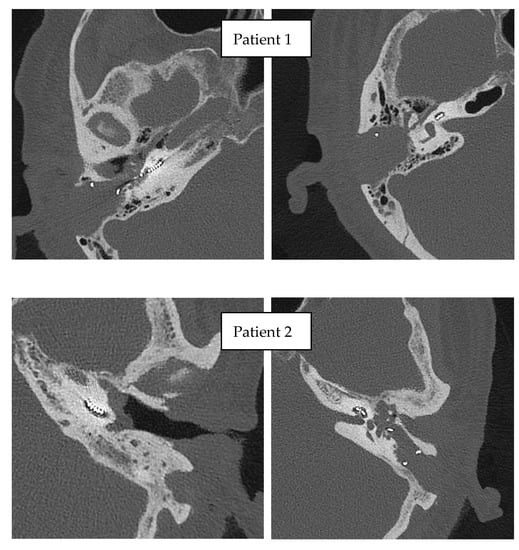

3.3. Imaging